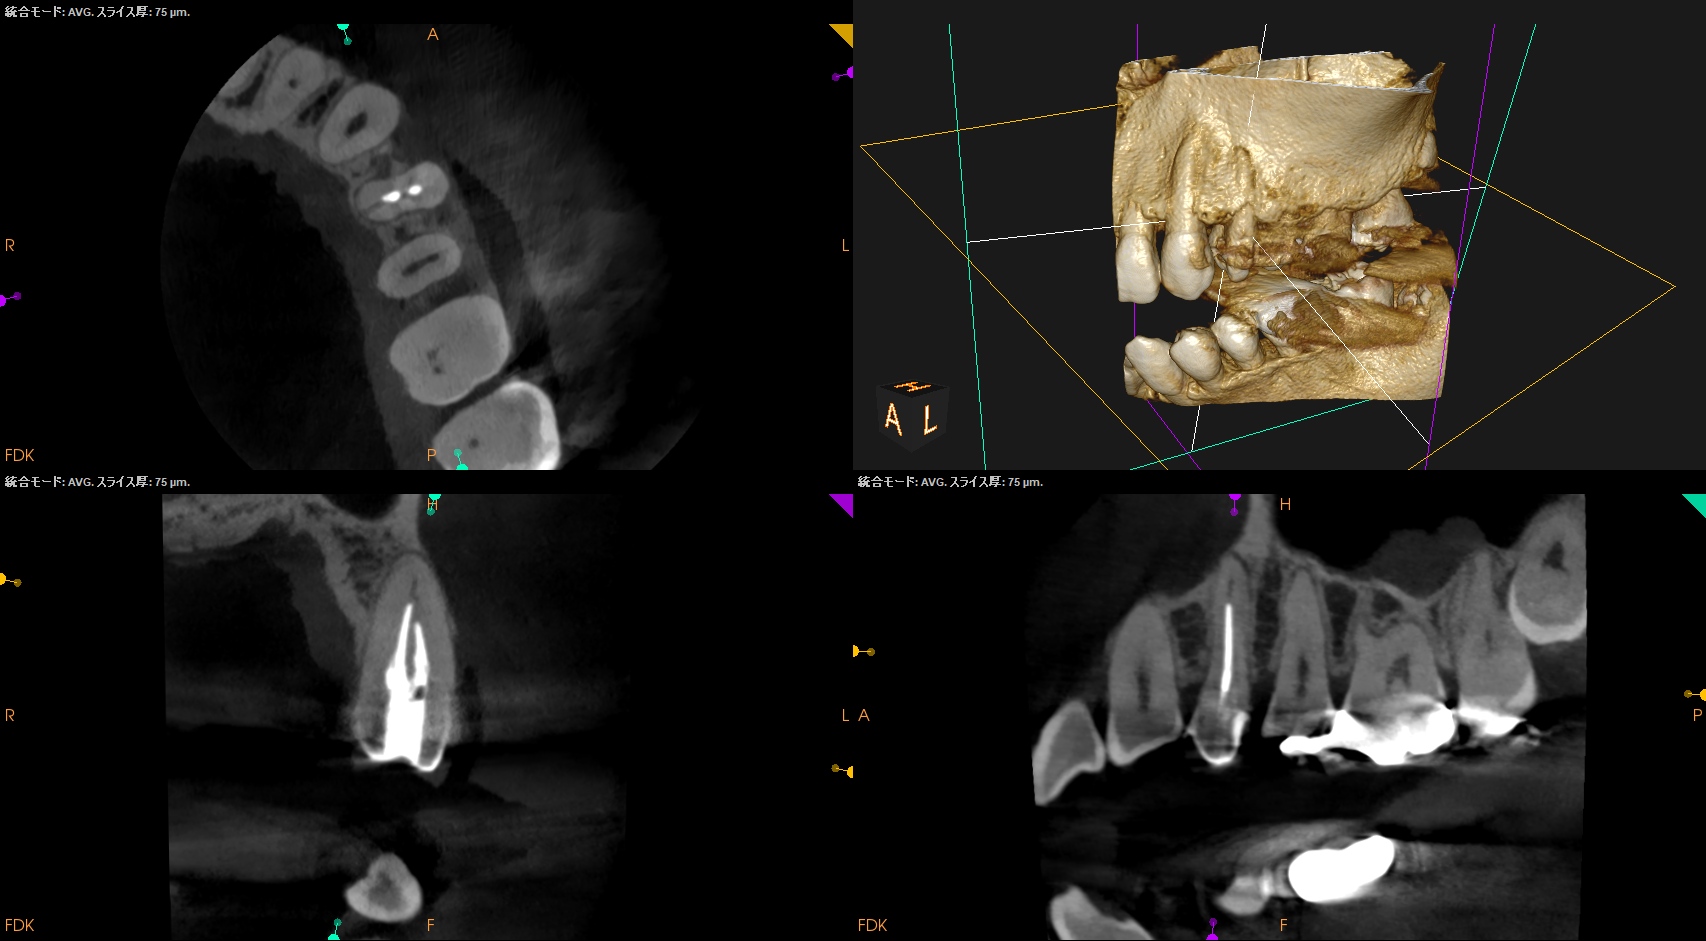

以下のようなケースでも可能なのだろうか?

私(当時Resident)も、

その後の二人のEndodontist(“自称”ではなく、“米国歯内療法学会”が認定する“Endodontist”である)も穿通させられなかったのだ。

何が言いたいか?と言えば、

全ての根管が穿通するとは限らない

ということである。

例えPAやCBCTで根管が見えていても、だ。